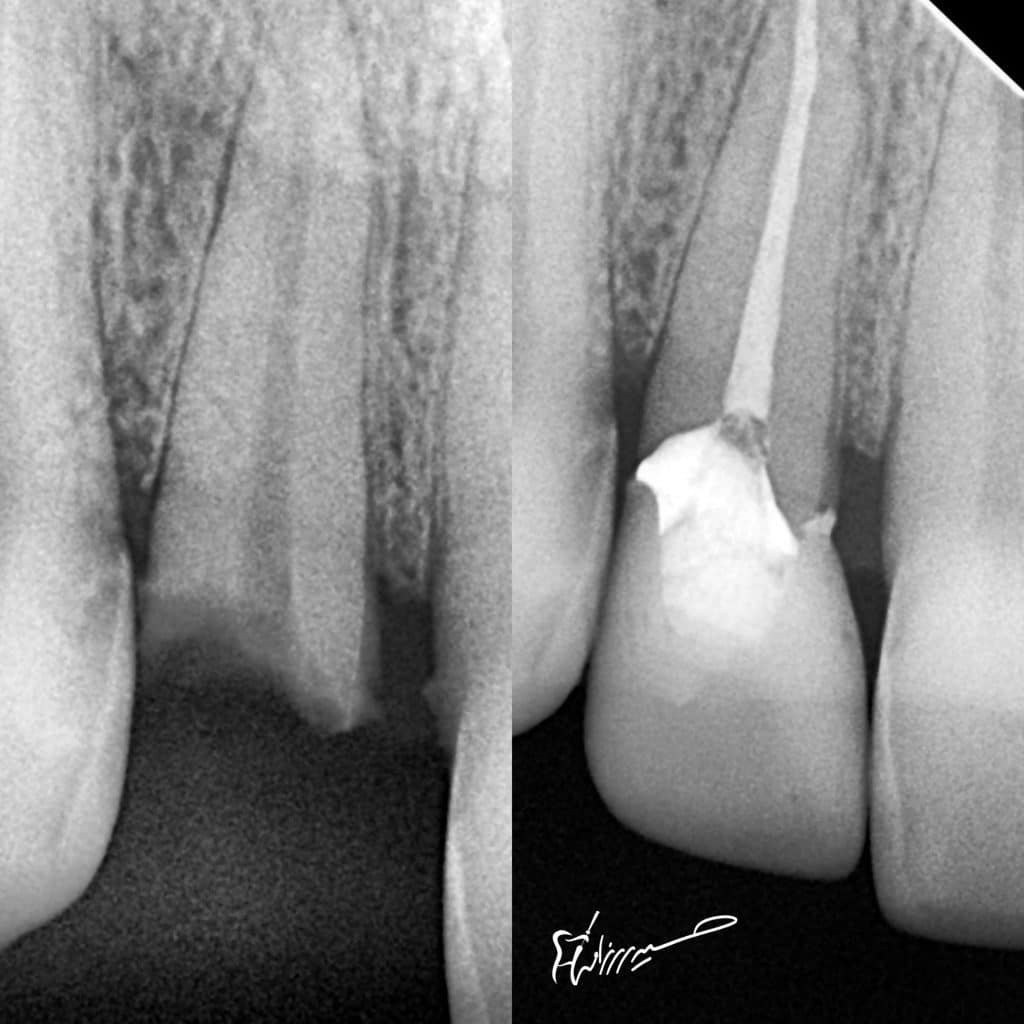

The first comment when you see cases like this is : bad prognosis! , it will fall soon ! Where is the fiber post ?!

CDD for definite caries removal

DWT for optimum dentin bond